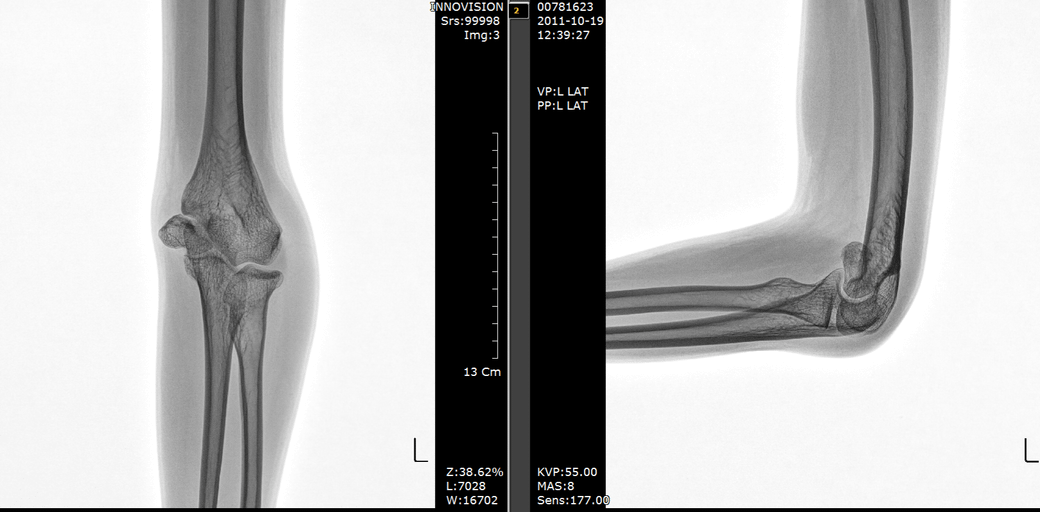

엑스레이에서도 팔꿈치 관절의 바깥쪽 일부가 돌출된 것이 관찰되는 데

이것을 교정한다고 해서 통증이 사라질 지에 대해 정형외과에서도 확신이

없는 것으로 생각됩니다. 진통제를 복용하면서 팔꿈치 주변으로 근육을 충분히

이미 과거 골절로 인해서 부정유합 및 불유합이 일어난것으로보입니다.

ulnar 뼈와 맞닫는 윗팍뼈 (humerous) 의 cepitellum 부위에 골절이 되셨던것 같습니다. 성장판을 다쳐서 해당 부위는 성장이 더뎌서 다른뼈와 구조상 맞지 않아질 수 있습니다.